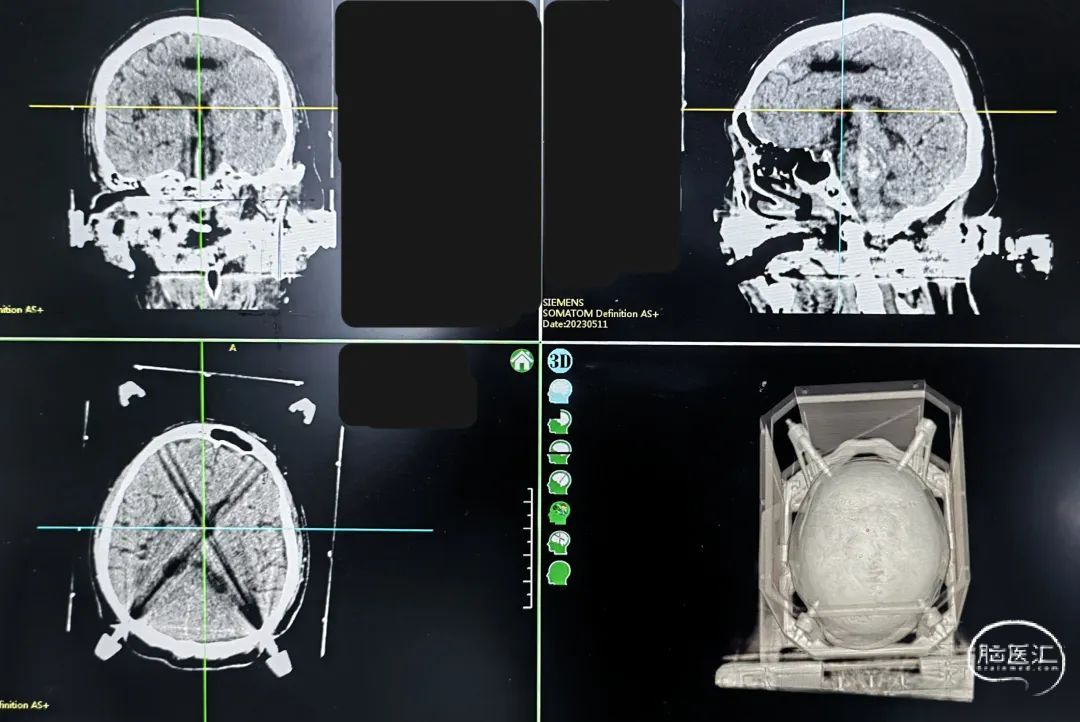

一口双孔,平行植入脑室引流管,测算脑室引流管植入靶点

双靶点

经额入路切口,可去除术侧额部头钉

血肿腔引流管引流出暗红色血肿,脑室引流液淡血性

脑室及血肿腔平行双管

术后尿激酶应用,术后3天复查CT,血肿引流满意